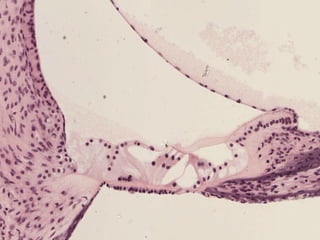

Células Pilosas

Membrana Vestibular

Órgano de

Corti

Escala Timpánica

Escala Vestibular